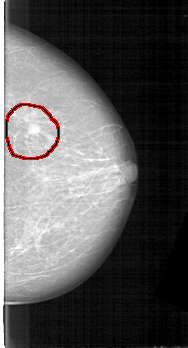

D_4125_1.RIGHT_CC

FILE: D_4125_1.RIGHT_CC.OVERLAY

TOTAL_ABNORMALITIES 1

ABNORMALITY 1

LESION_TYPE MASS SHAPE OVAL MARGINS ILL_DEFINED

ASSESSMENT 3

SUBTLETY 4

PATHOLOGY MALIGNANT

TOTAL_OUTLINES 1

BOUNDARY